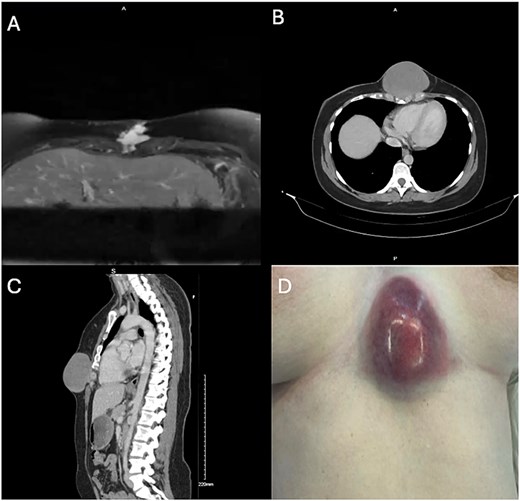

The patient underwent a combined thoracic and plastic surgery case with chest wall resection, including the inferior sternum and costal cartilage, followed by reconstruction with Permacol mesh and a pedicled latissimus dorsi musculocutaneous flap. An incision was made around the tumor with wide margins, with dissection down to the chest wall (Fig. 2A). The intercostal spaces were entered and the costal cartilage resected circumferentially around the inferior sternum. A margin of costal cartilage was left intact bilaterally to avoid disrupting continuity of the thoracic cage (Fig. 2B). A transverse sternotomy was then performed and the tumor was removed en bloc along with the inferior sternum (Fig. 2C).

A: Incision around tumor with wide margin. B: Costal resection. C: Resected specimen. D: Large (14 × 12 cm) anterior thoracic defect.